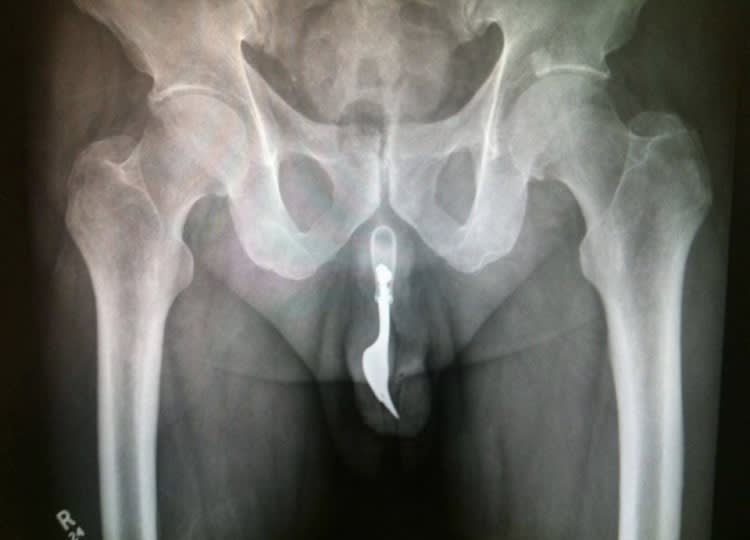

regardez moi ça 

(Le premier c'est pas un concombre , c'est une courgette, le 3eme c'est une lampe torche)

Quelqu'un a t il perdu ses clés ?